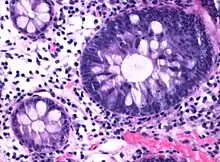

| Micrograph of hyperplastic polyp. | |

Histopathologically, there are two main types of hyperplastic polyps, which have genetic differences, as well as different histologic structure, but no significant differences clinically.[4] The two main types of hyperplastic polyps are microvesicular mucin-rich type and goblet cell-rich type.[1] A mucin-poor type with eosinophilic cytoplasm, which is rare, was previously described.[4] However, the mucin poor type is no longer considered a distinct subtype.[1]

The luminal portion has a serrated (“saw tooth”) appearance formed by tufts or folds of abundant apical cytoplasm. It contains glands with star-shaped lumina.[4] There are crypts that are elongated but straight, narrow and hyperchromatic at the base. All crypts reach to the muscularis mucosae.[4] The basement membrane is frequently thickened.[4]

Elongated, fat crypts and little to no serration. Therefore, they may not be obvious without comparing to adjacent normal intestinal wall.[4]

They are filled with goblet cells, extending to surface, which commonly has a tufted appearance.[4]